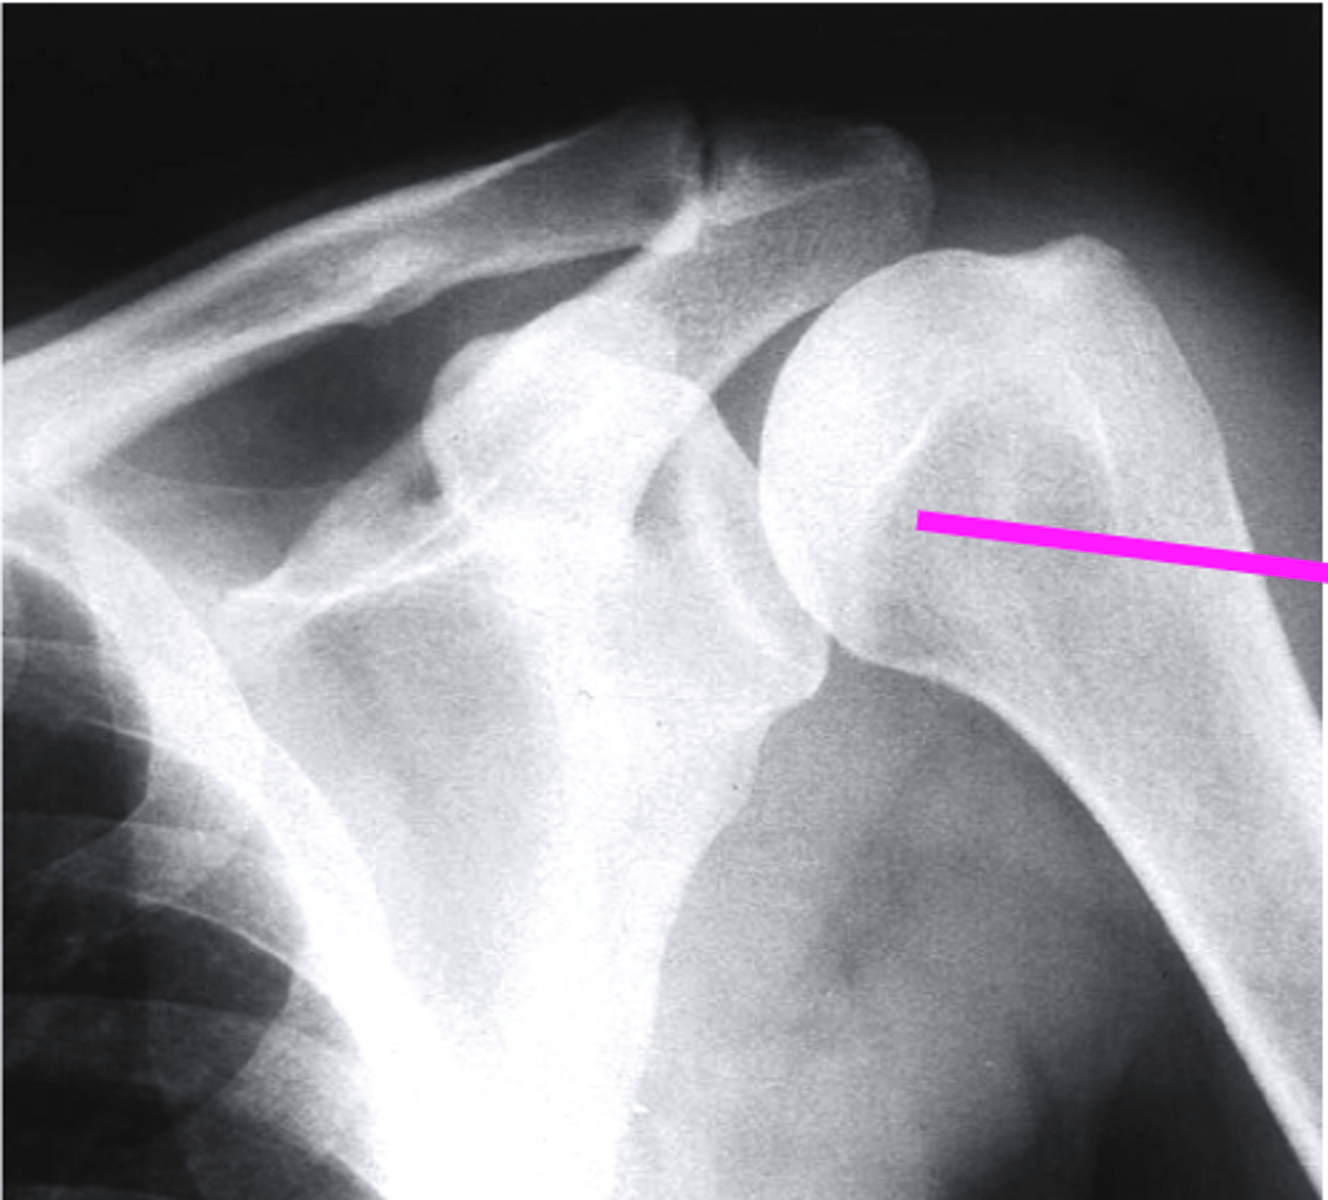

shoulder axillary

what view is this?

clavicle

what does the pink line point to?

the coracoid process

the glenoid fossa

acromion

humeral head